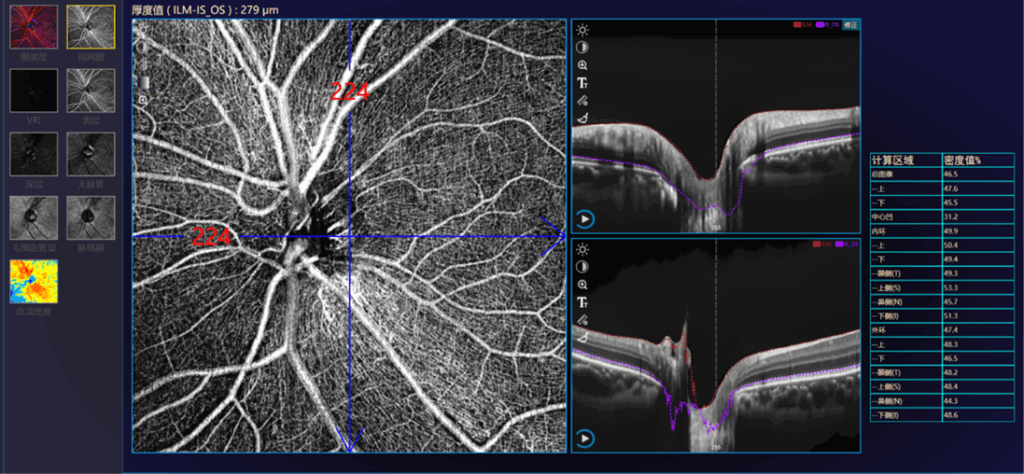

Análisis Macular Glaucomatoso

• Análisis de grosor GCA

• Análisis de grosor GCC

Tomografía de Coherencia Óptica y Angiografía

(OCT-A)

Alta velocidad y Ultra alta resolución

Sistema de Screening de enfermedades oculares con Inteligencia Artificial que evalúa lesiones comunes del polo posterior y optimiza la eficiencia del examen.